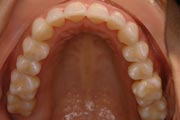

Crowding

After